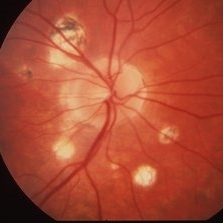

Histoplasmosis

Histoplasmosis

Mar 27 2019 by Gary R. Cook, MD, FACS

24-year-old white female with presumed ocular histoplasmosis (POHS) demonstrating minimal peripapillary atrophy but 3 atrophic histo spots around the optic nerve of her left eye; patient was asymptomatic; V.A.= 20/20.

Imaging device: Topcon VT-50

Condition/keywords: atrophic spot, ocular histoplasmosis syndrome (OHS), presumed ocular histoplasmosis syndrome (POHS)